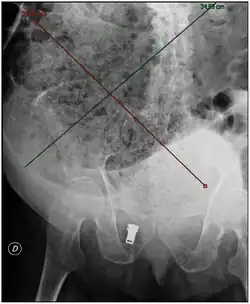

Plain abdominal X-ray showing a large fecal impaction extending from the pelvis upwards to the left subphrenic space and from the left towards the right flank, measuring over 40 cm in length and 33 cm in width.